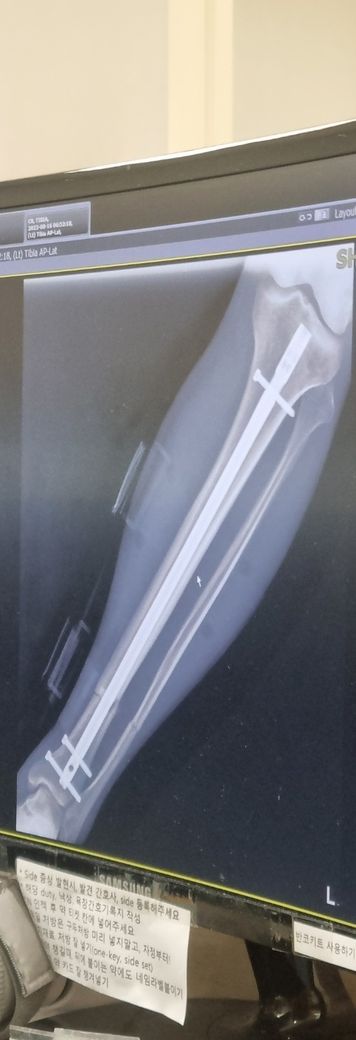

정강이 경비골 분쇄골절로 금속정 삽입. [제거 수술 다른병원에서 해도 되나요?]

사진은 골절 수술 하고 얼마되지 않았을 때 사진 입니다. 정강이 경비골 분쇄골절로 사진의 경골에 금속정 삽입하고 비골은 비고정입니다.

• 1번 째 사진